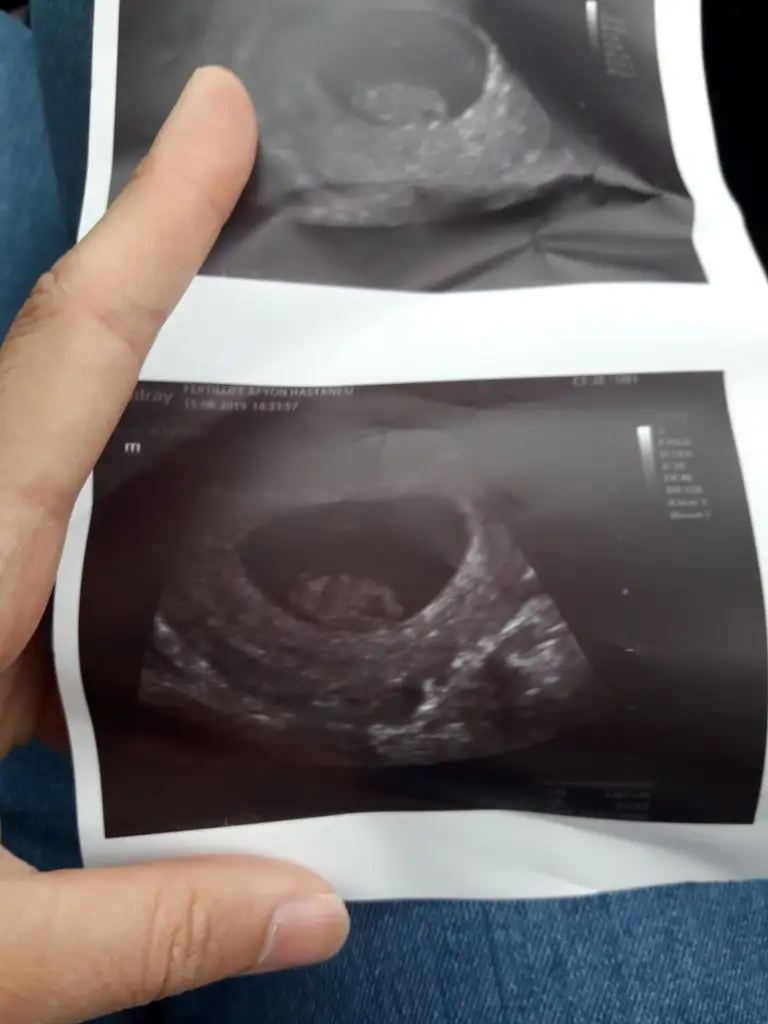

Ayy maşallah canım yaaa darısı yarına başıma inşallah8+4 dedi doktor canim kesesiyle uyumlu dedi. Elleri ayaklari tomurcuklanmis cok sukurher sey cok iyi dedi masallah fotosu var eve gidince atarim